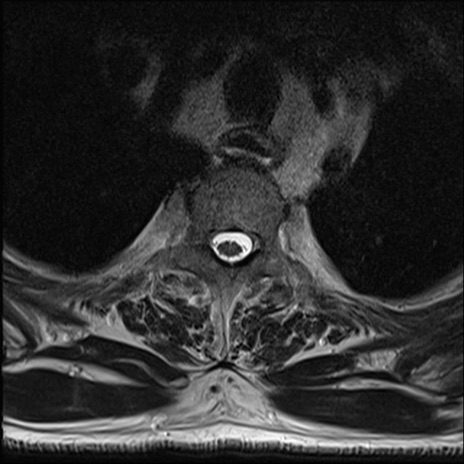

【整形】TIPS症例7 頚椎MRI T2WI(横断像)

頚椎MRI

矢状断像と横断像